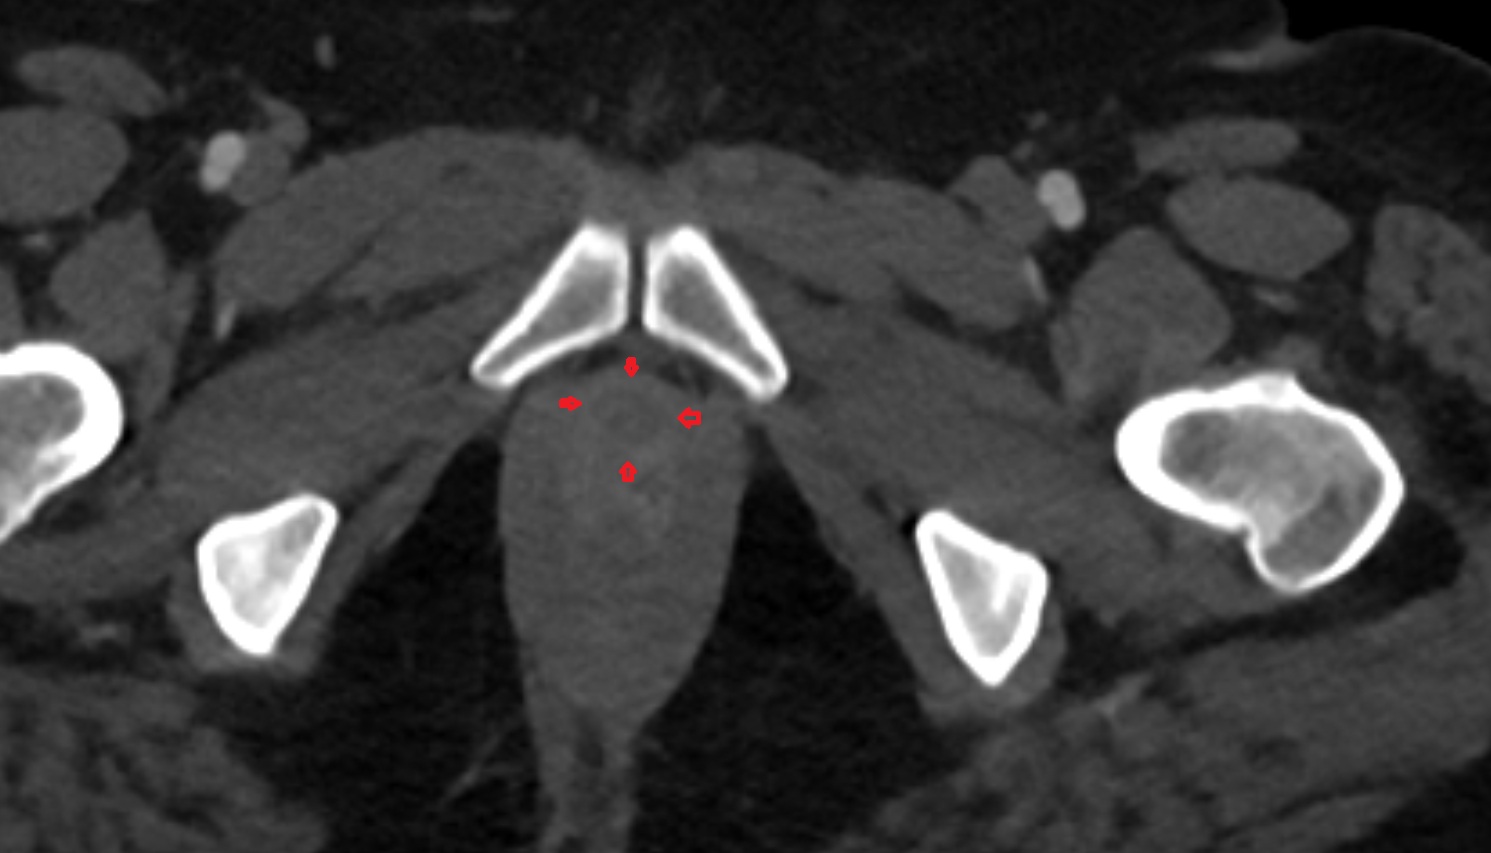

- Peripheral zone of prostate

- Anterior Fibromuscular Stroma of prostate

- Central zone of prostate

- Transitional zone of prostate